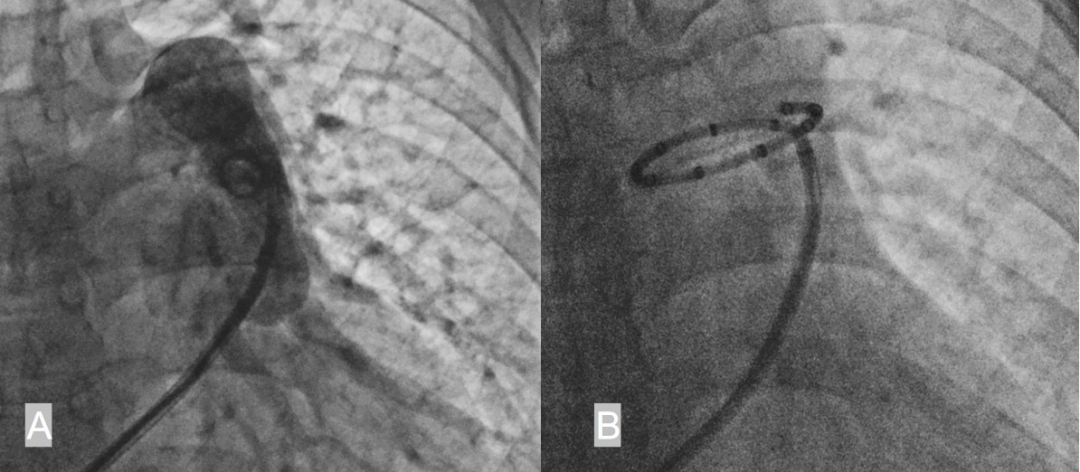

病例1是一名33岁的女性,因反复胸闷气促1年就诊,心超提示有28mm的继发孔型房缺,肺动脉收缩压高达98mmHg,右心导管检查提示患者的平均肺动脉压力为48 mmHg,PVR为5.4 Wood U,Qp/Qs=1.8。经过6个月的双联肺动脉靶向药物治疗,患者的PASP仍高达80mmHg,随后升级为三联(马昔腾坦+利奥西呱+司来帕格)治疗,6个月后封堵尝试失败。因此,我们为患者行PADN治疗,在肺动脉主干与左肺动脉交接处行射频消融治疗,术后随访2个月,患者的平均肺动脉压力降至40 mmHg,PVR为3.2 Wood U,Qp/Qs=2.6。最后成功用32mm的房缺封堵器进行了封堵,封堵术后3个月心超随访PASP成功降至43mmHg。

病例2是一名29岁的女性,反复胸闷气促1年余,心超提示15mm大小的继发孔型房缺,肺动脉收缩压达66mmHg,右心导管检测结果提示平均肺动脉压力为46 mmHg,PVR为7.59 Wood U,Qp/Qs=1.6。经过一个月的三联靶向药物治疗,心超的PASP仍高达65mmHg,因此,我们为患者行PADN治疗,在肺动脉主干与左肺动脉交接处行射频消融治疗,术后患者的平均肺动脉压力降至35 mmHg, PVR降至3.9 Wood U,最终成功用26mm的封堵器进行封堵。